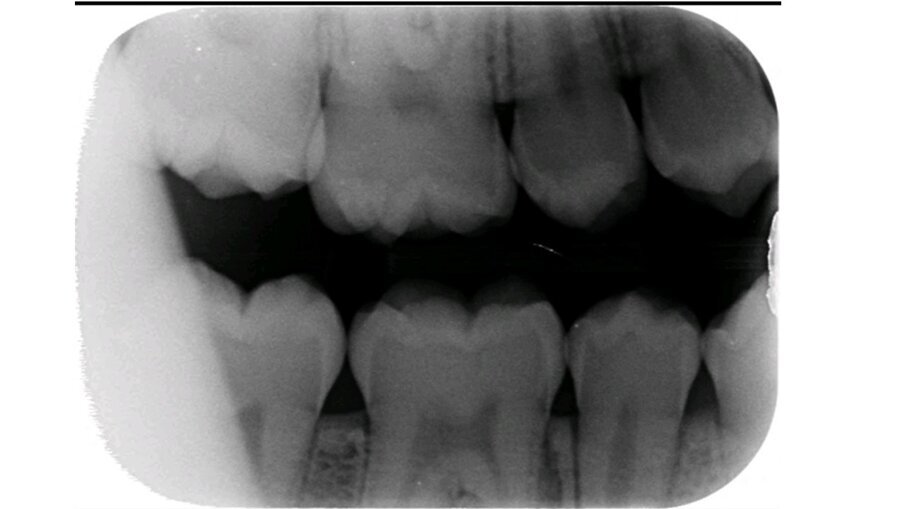

Het eerste kind waarbij wij NRC toepasten was 6 jaar. Op de bitewings werden cariëslaesies bij alle vlakken van de aangrenzende melkmolaren gediagnosticeerd. Met de ouders werd besproken wat onze plannen waren. Zij gingen hiermee akkoord. In de volgende zitting werden de 8 vlakken beslepen (afbeelding 1a-b). De behandeling verliep probleemloos en werd goed geaccepteerd. Maar in het vervolgtraject hebben we steken laten vallen. De voorlichtende communicatie gebeurde hoofdzakelijk traditioneel. De terugkomtermijn besloeg een paar keer achter elkaar een interval van bijna een jaar. Daar verander je geen gedrag mee. De verslaggeving ontbrak een aantal keren. Bijna 6 jaar later werd geconstateerd dat er veel plaque aanwezig was. De wisseling had inmiddels plaatsgevonden. Restauratief of chirurgisch ingrijpen is sinds NRC werd toegepast niet nodig geweest en de bitewings vertonen geen cariësactiviteit (afbeelding 2a-b). Ook waren geen sealants noodzakelijk geweest.

Afbeelding 2a. Bitewings van de blijvende dentitie.

Afbeelding 2b. Bitewings van de blijvende dentitie.